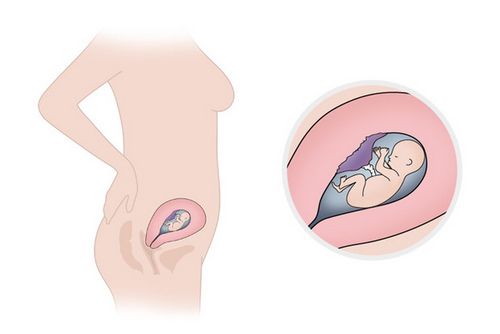

Початок 16-му тижні вагітності, Ви можете, з гордістю похвалиться невеликим животиком. Багато жінок люблять цей етап вагітності, коли у них досить видно животик, щоб відчувати себе вагітною, але не настільки він великий, щоб відчувати незграбність від живота.

Ви можете почати відчувати до 16-му тижні вагітності рухи плоду. Це, швидше за все, станеться, якщо у Вас не перша вагітність або якщо мама має тендітною статурою. Ці перші рухи часто описують, як бульбашки газу. Ви, можете, відчувати ці відчуття і навіть не зрозуміти, що це Ваша дитина. Раз Ви досягли 16-му тижні вагітності, доктор буде говорити, що Ви не повинні спати на спині. Сон стає на боці. Матка продовжує рости і важить близько 250 грам. Плацента також зростає, і Ваше тіло виробляє підвищену кількість навколоплідних вод, які допомагають захистити дитину під час вагітності. Зараз Ваш організм отримує близько 300 мл амніотичної рідини, що оточує Вашого малюка. Материнський організм виробляє на 50% більше крові, що призводить до підвищення циркуляції крові по тілу. Через збільшення циркуляції крові шкіра на обличчі може стати більш яскравою. Ваш наступний допологової візит до лікаря, може бути призначений протягом найближчих декількох тижнів. В ході цього візиту, Ваш лікар може рекомендувати деякі тести, включаючи: ультразвук, рівень альфа-фетопротеїну, потрійний тест, амніоцентез. До 16-му тижні вагітності оптимальна прибавка в вазі становить близько 2,5 кг. Апетит збільшується в міру зростання плоду. Самопочуття призводить до значного покращення, Ви відчуваєте більше радісного хвилювання.

Малюк активно набирає вагу і зростанні. До 16-му тижні вагітності він виріс до 16 см в довжину і близько 80-120 грам у вазі. У найближчі кілька тижнів, Ваше чадо буде подвоювати свою масу, і додавати в зростанні. Зараз він з велике авокадо. Ніжки стають довшими ручок, на пальчиках сформовані нігтики, які довгі і гострі. Голова зменшилася в порівнянні з тілом. До 16 тижня вагітності Ваша дитина досить сильний, щоб тримати, рівно голову. Його / її вуха і очі розташовані у своїй остаточній позиції.